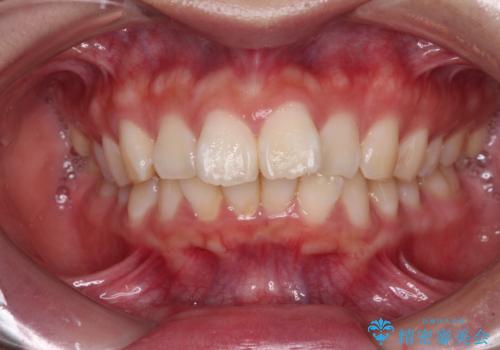

目立つ八重歯を非抜歯矯正で整える 目立たないワイヤー矯正

担当医 藤巻太一朗